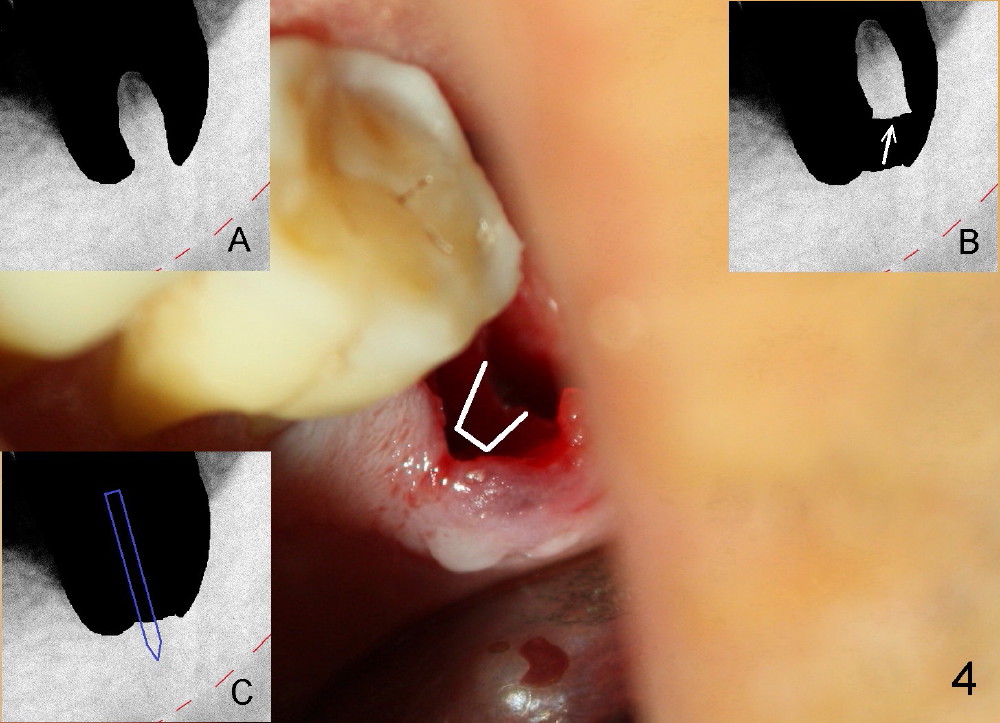

A 51-year-old man has generalized chronic periodontitis. The mesial root of #18 has vertical fracture (Fig.1*) with infection. The patient agrees extraction (Fig.2) and immediate implant. The septum is thin. The pilot drill drops into either the mesial (Fig.3) or distal sockets. Furthermore it is difficult to control pain probably due to severe infection (Fig.2 >: mesiobuccal erythema and edema). Repeated local infiltration does not alleviate pain associated with drilling. Block anesthesia has to be administered (one carpule of 2% Lidocaine with 1:100,000 Epinephrine). Damage to the inferior alveolar nerve (Fig.1 red dashed line) increases. On the other hand, osteotomy through the socket of the tooth with periodontits is easier because of shallow socket. Retraction of the buccal gingiva can reveal the bottom of the socket. We will increase the depth slowly until a tap obtains initial stability. The worst scenario is that active hemorrhage from the socket bottom is encountered initially. The nerve injury can be reduced minimally.

Now where to initiate osteotomy? Since the mesial crest is much lower than the distal (compare arrowheads in Fig.1), placement of an implant in the mesial socket is a good approach, whereas placement in the distal socket is not good for restoration (cantilever). The thin septum is slippery to drill penetration. What should we do?

How about flatten the septum (Fig.4 white lines; from inset A (post extraction) to B)? When the septum is level with the mesial and distal sockets, a drill easily penetrates the middle of the socket (Fig.3 inset C). With strict control of depth, the osteotomy increases until a 6x14 mm tap gets initial binding to the socket (Fig.5: depth 11 mm). After increase in the depth by 1-2 mm, PA is taken with a 7x14 mm tap (Fig.6). There is a gap that the tap or the corresponding implant can engage further (between arrowheads). After increase in the diameter in the bottom of the osteotomy, a 7x11 mm implant is placed with insertion torque between 45 and 50 Ncm; the threads of the implant have tight contact with the bone (Fig.7). With the large diameter implant, the socket opening is closed without too much tension (Fig.8). The wound is protected with perio dressing. Postop there is no paresthesia. Pain is controlled by Hydrocodon/Acetaminophen. A long acting local anesthetic (Marcaine) should have been used immediately postop. Next morning, the patient is pain free. A short implant should be used in a critical area such as the lower 2nd molar where the inferior alveolar nerve is nearby. However, the implant is found unstable 1 month postop.